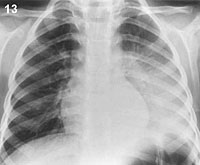

ESQUEMA 13 Comentario placa 13 En este caso, es posible seguir el borde cardíaco izquierdo que se destaca con claridad sobre la sombra de condensación, indicando una falta de contigüidad. Esto significa que la condensación está en el lóbulo inferior |